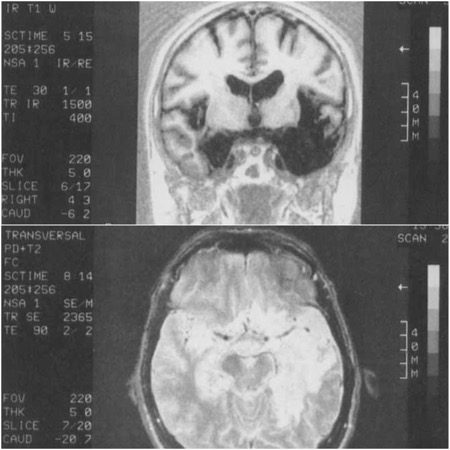

En 1991, se hizo una resonancia magnética que mostró anormalidades en estructuras hipocampales, amígdalas, sustancia innominada, cuerpos mamilares, lóbulos temporales, fórnix izquierdo, circunvolución temporal, parte anterior superior de la circunvolución temporal izquierda e ínsula izquierda. Además, se encontró una leve anomalía en la parte posterior media de la circunvolución temporal izquierda, corteza frontal medial izquierda, cuerpo estriado izquierdo, ínsula derecha, fórnix derecho y parte inferior anterior de la circunvolución temporal derecha.

El tercer ventrículo y ambos ventrículos laterales se consideraron significativamente dilatados. Por otro lado, el tálamo permaneció intacto y no se encontró ninguna otra anomalía del lóbulo frontal (además de la anomalía frontal medial izquierda mencionada) (ver Figura 1).